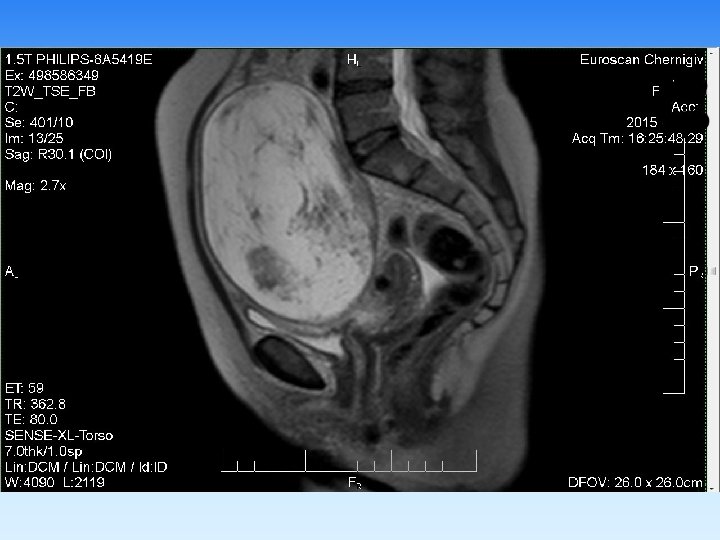

Примеры визуализаций

§ В неврологической практике МРТ позволяет диагностировать аномалии развития, воспалительные, дисциркуляторные, неопластические процессы головного и спинного мозга, а также его оболочек. Кроме того, незаменимым метод является в диагностике патологии межпозвонковых дисков, паравертебральных мягких тканей, а также в скрининговой диагностике патологии сосудов головы и шеи. § В ортопедии МРТ показано при любой патологии гиалинового хряща, внутрисуставных связок, менисков, ротаторной манжеты плечевого сустава, синовиальных складок, что позволяет достоверно диагностировать их разрывы, отек, инфильтрацию. § При исследовании брюшной полости МРТ позволяет диагностировать заболевания печени, желчевыводящих протоков (режим холангиографии без применения контраста обеспечивает визуализацию холедоха, вирсунгова протока на всем протяжении), поджелудочной железы, селезенки, надпочечников, лимфатических узлов брюшной полости. § Широко используется МРТ в гинекологии и урологии, в маммологии метод позволяет диагностировать объемные процессы и их распространенность.

Имеющийся у нас набор катушек томографа PHILIPS Ahieva позволяет визуализировать с высоким качеством: § головной мозг (в т. ч. аномалии гипофиза, с применением контрастирования); § артерии и вены головного мозга; § орбиты и зрительные нервы; § все отделы позвоночного столба; § тазобедренный, коленный, плечевой, локтевой, височнонижнечелюстной, суставы; § лучезапястный сустав , запястно-пястный отделы кисти, стопы и голеностопные суставы; § почки и надпочечники; § печень, поджелудочную железу, селезенку; § предстательную железу, яички, мочевой пузырь, матку, яичники: § мягкие ткани тела.